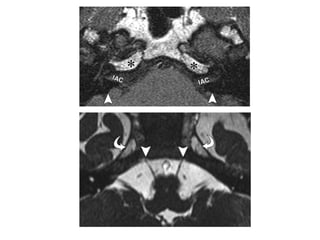

Note the high-signal-intensity fatty marrow in the anterior

petrous apex (*) and the low signal intensity of the denser

posterior petrous apex (arrowheads).

In pneumatized or sclerotic apices, the anterior portion may

normally demonstrate low signal intensity due to the absence

of fatty marrow.